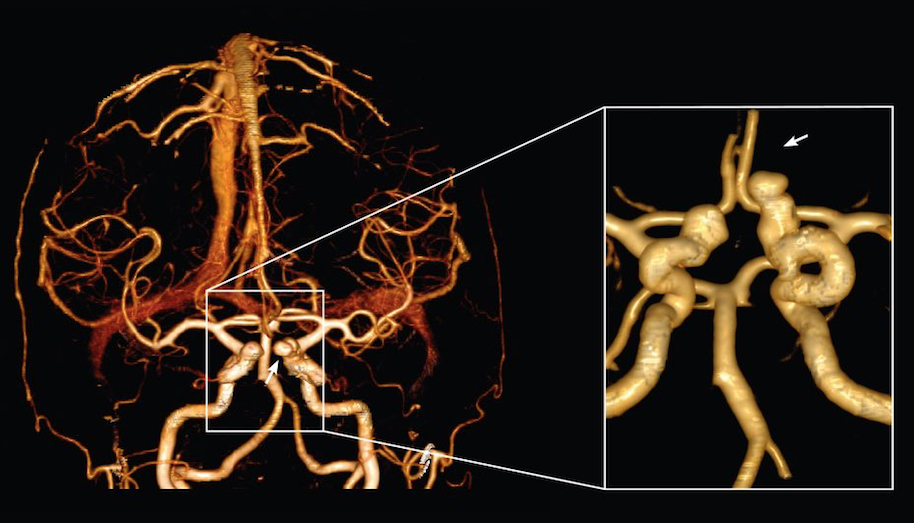

Šta je CT koronarografija?

To je metoda prikaza malih arterija koje hrane  srčani mišić, upotrebom CT skenera, koji prikazuje protok krvi u koronarnim arterijama i kompjuterskog softvera da bi se dobio odgovarajući trodimenzionalni prikaz. CT angiografija je neinvazivni način da se prikažu zidovi koronarnih arterija I nadju eventualni aterosklerotski plakovi, što pomaže liječniku u odredjivanju rizika srčanog udara.